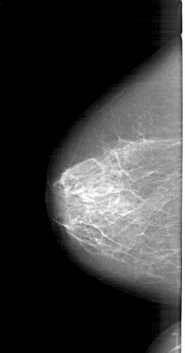

A_1390_1.RIGHT_CC

LEFT_CC LINES 5986 PIXELS_PER_LINE 3136 BITS_PER_PIXEL 12 RESOLUTION 43.5 NON_OVERLAY